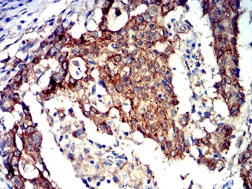

PRKAA2 Mouse Monoclonal antibody[8E11H5]

IHC    1/100 - 1/500